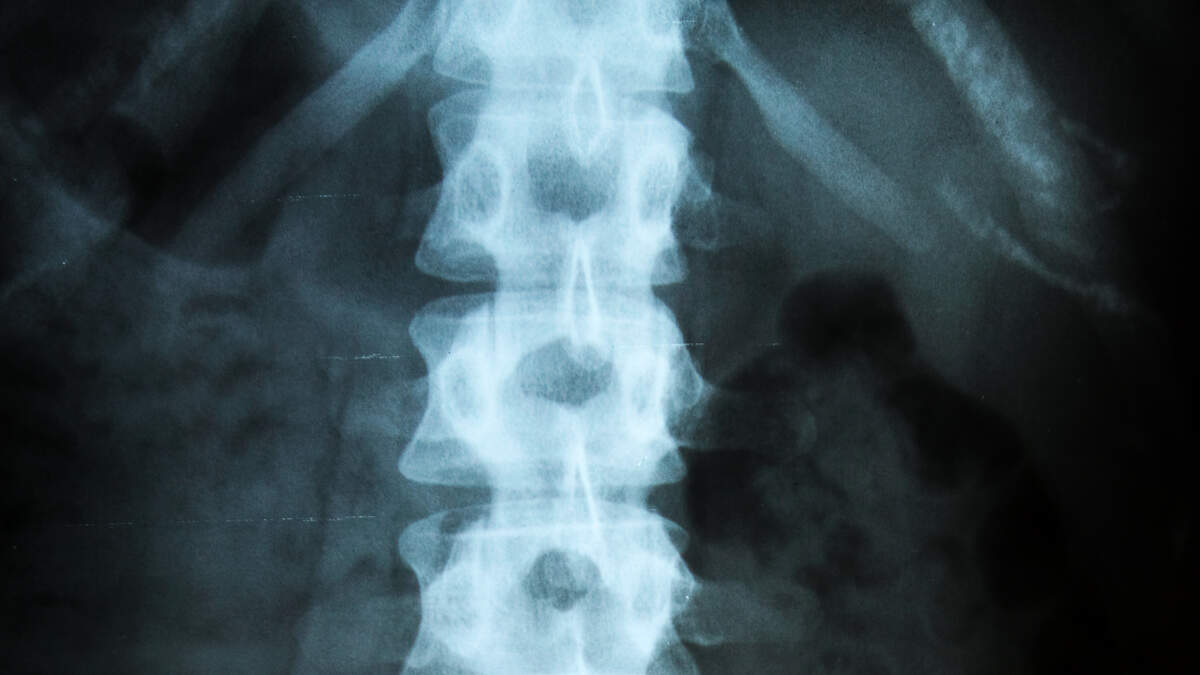

He told his mother that he was holding the Air Pod in his mouth while his grandmother was driving and he accidentally inhaled it. She posted a photo of the X-rays from the doctors at Children's Healthcare of Atlanta at Egelston showing the airpod in her son's stomach, fully intact. Doctors told her that it should pass through the boy's body on its own within a couple of days.